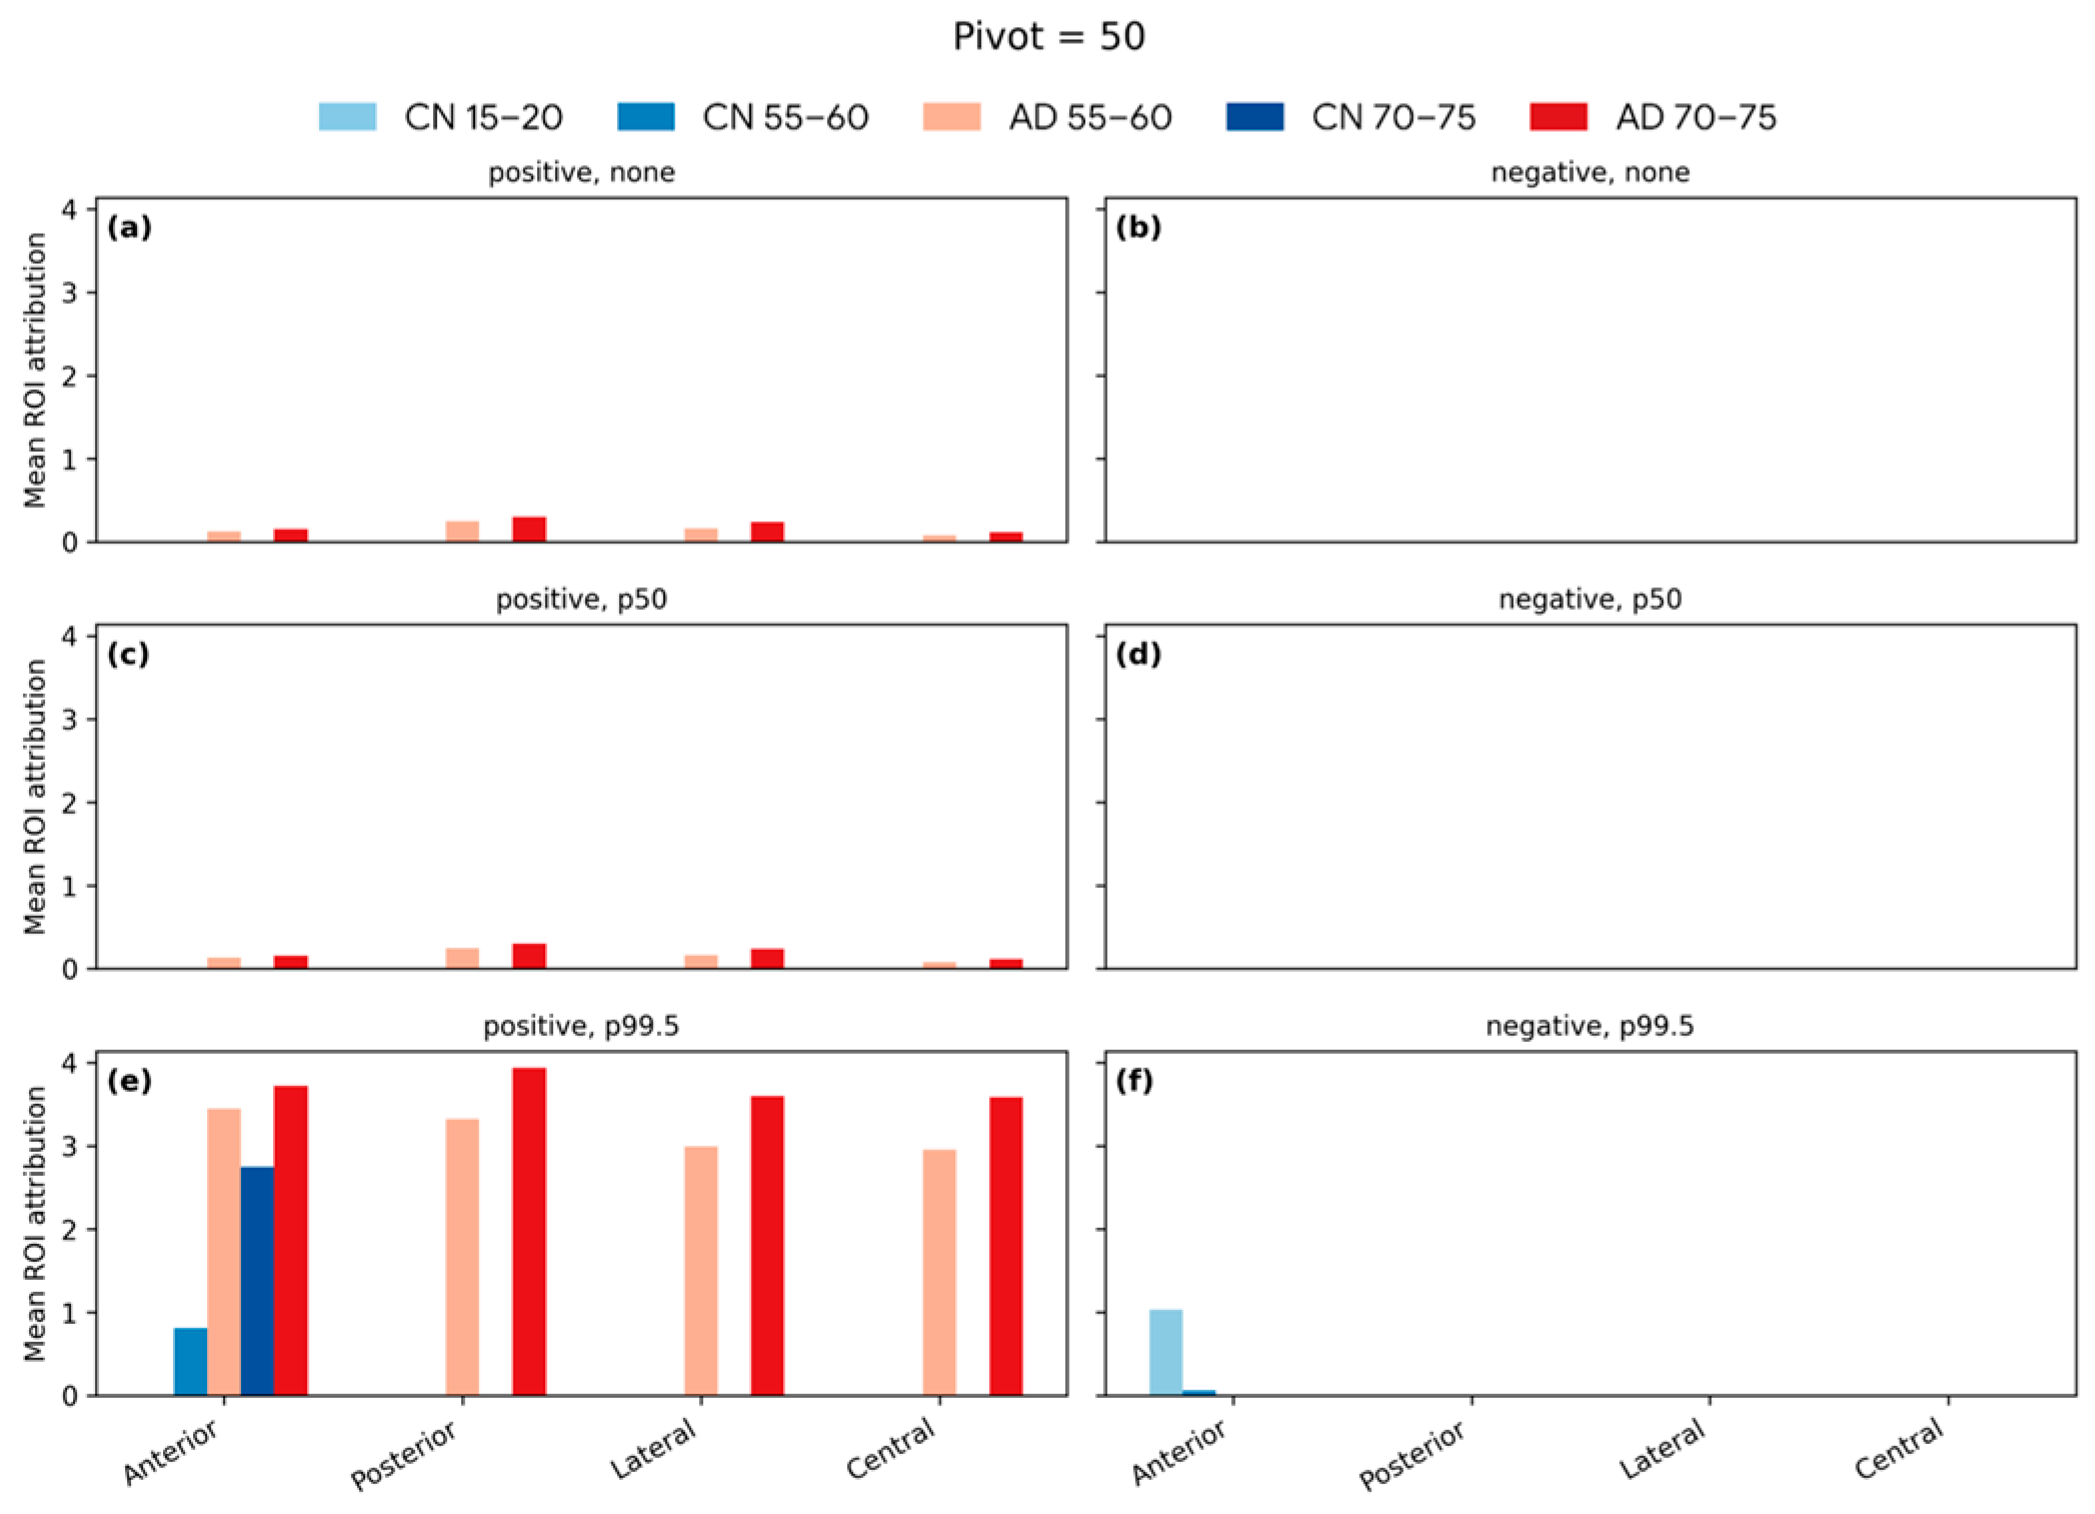

4.6. Softmax-Derived Brain Age Mapping Analysis